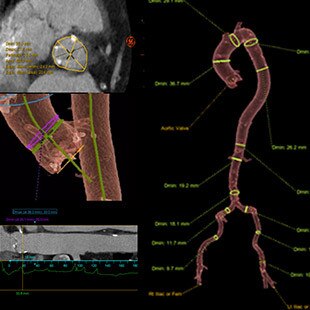

- La soluzione Valve ASSIST 2 comprende TAVI Analysis, HeartVision 2 e richiede una workstation AW con Volume Viewer, Volume Viewer Innova. Queste applicazioni sono vendute separatamente.